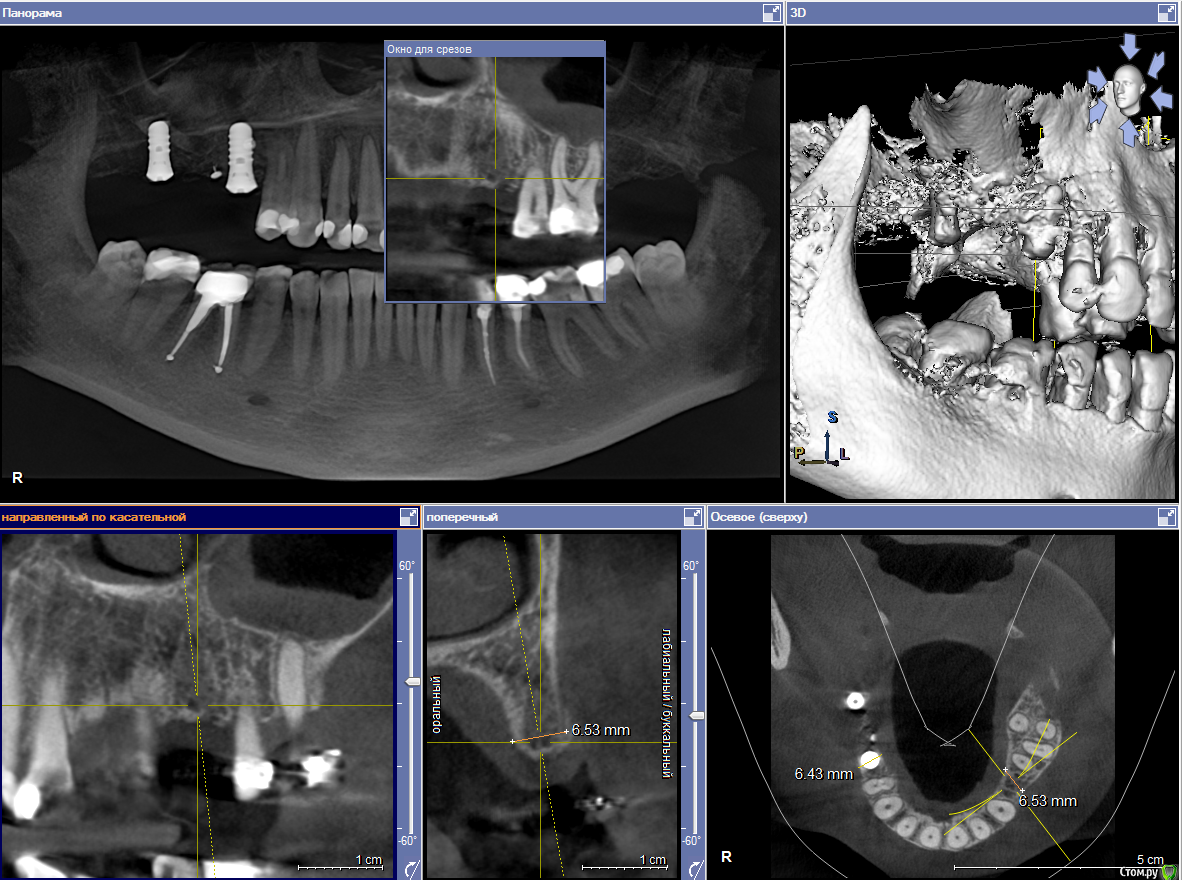

Хирургический план :  консервативное лечение у ЛОР специалистов

1) имплантация в позиции 15,17 з с закрытым синусом и незначительной НКР

2) коррекция слизистой в области 1-го сегм

3) имплантация с ССТ в позиции 24 з ( после дистализации 25,26 з), в области 27 з на момент  операции был гнойный синусит, отложили